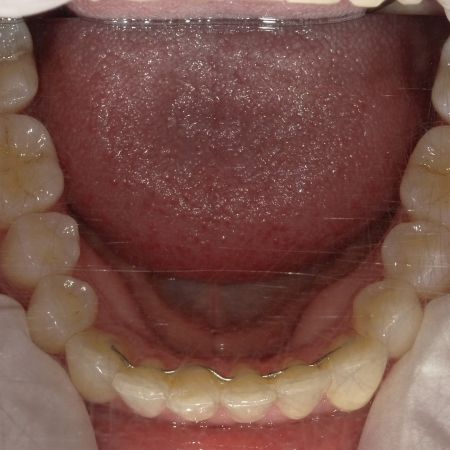

Nach der Behandlung

(Dauer der aktiven Behandlung: Im Oberkiefer 7 Monate, im Unterkiefer 1 Jahr, 4 Monate)

Sehr gute Stabilität nach 12 Jahren